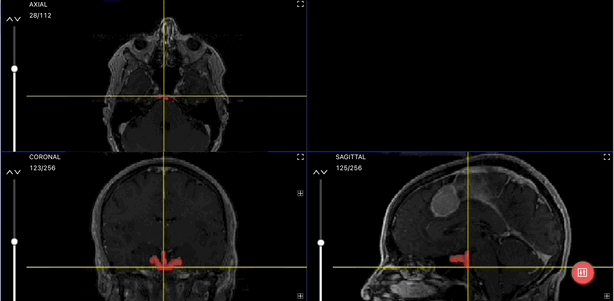

Brain Tumor Segmentation

Brain Tumor Detection (Source)

The region of interest for this problem is the area affected by the tumor in the brain. Once this area is identified and segmented, further studies can be performed. It greatly alleviates the burden on radiologists.

Multiplanar Translation & Crosshair

The crosshair allows you to gather your bearings in 3D space and to understand where your cursor is positioned relative to all views. It also allows you to synchronize all views in such a way that they all show the same pixel you are selecting with the crosshair. This is also known as multiplanar translation.

This isn’t just handy; it makes tasks like identifying things in medical images much easier. The crosshair and multiplanar translation help in both navigating in 3D space and simplifying image segmentation by making it more precise and straightforward.